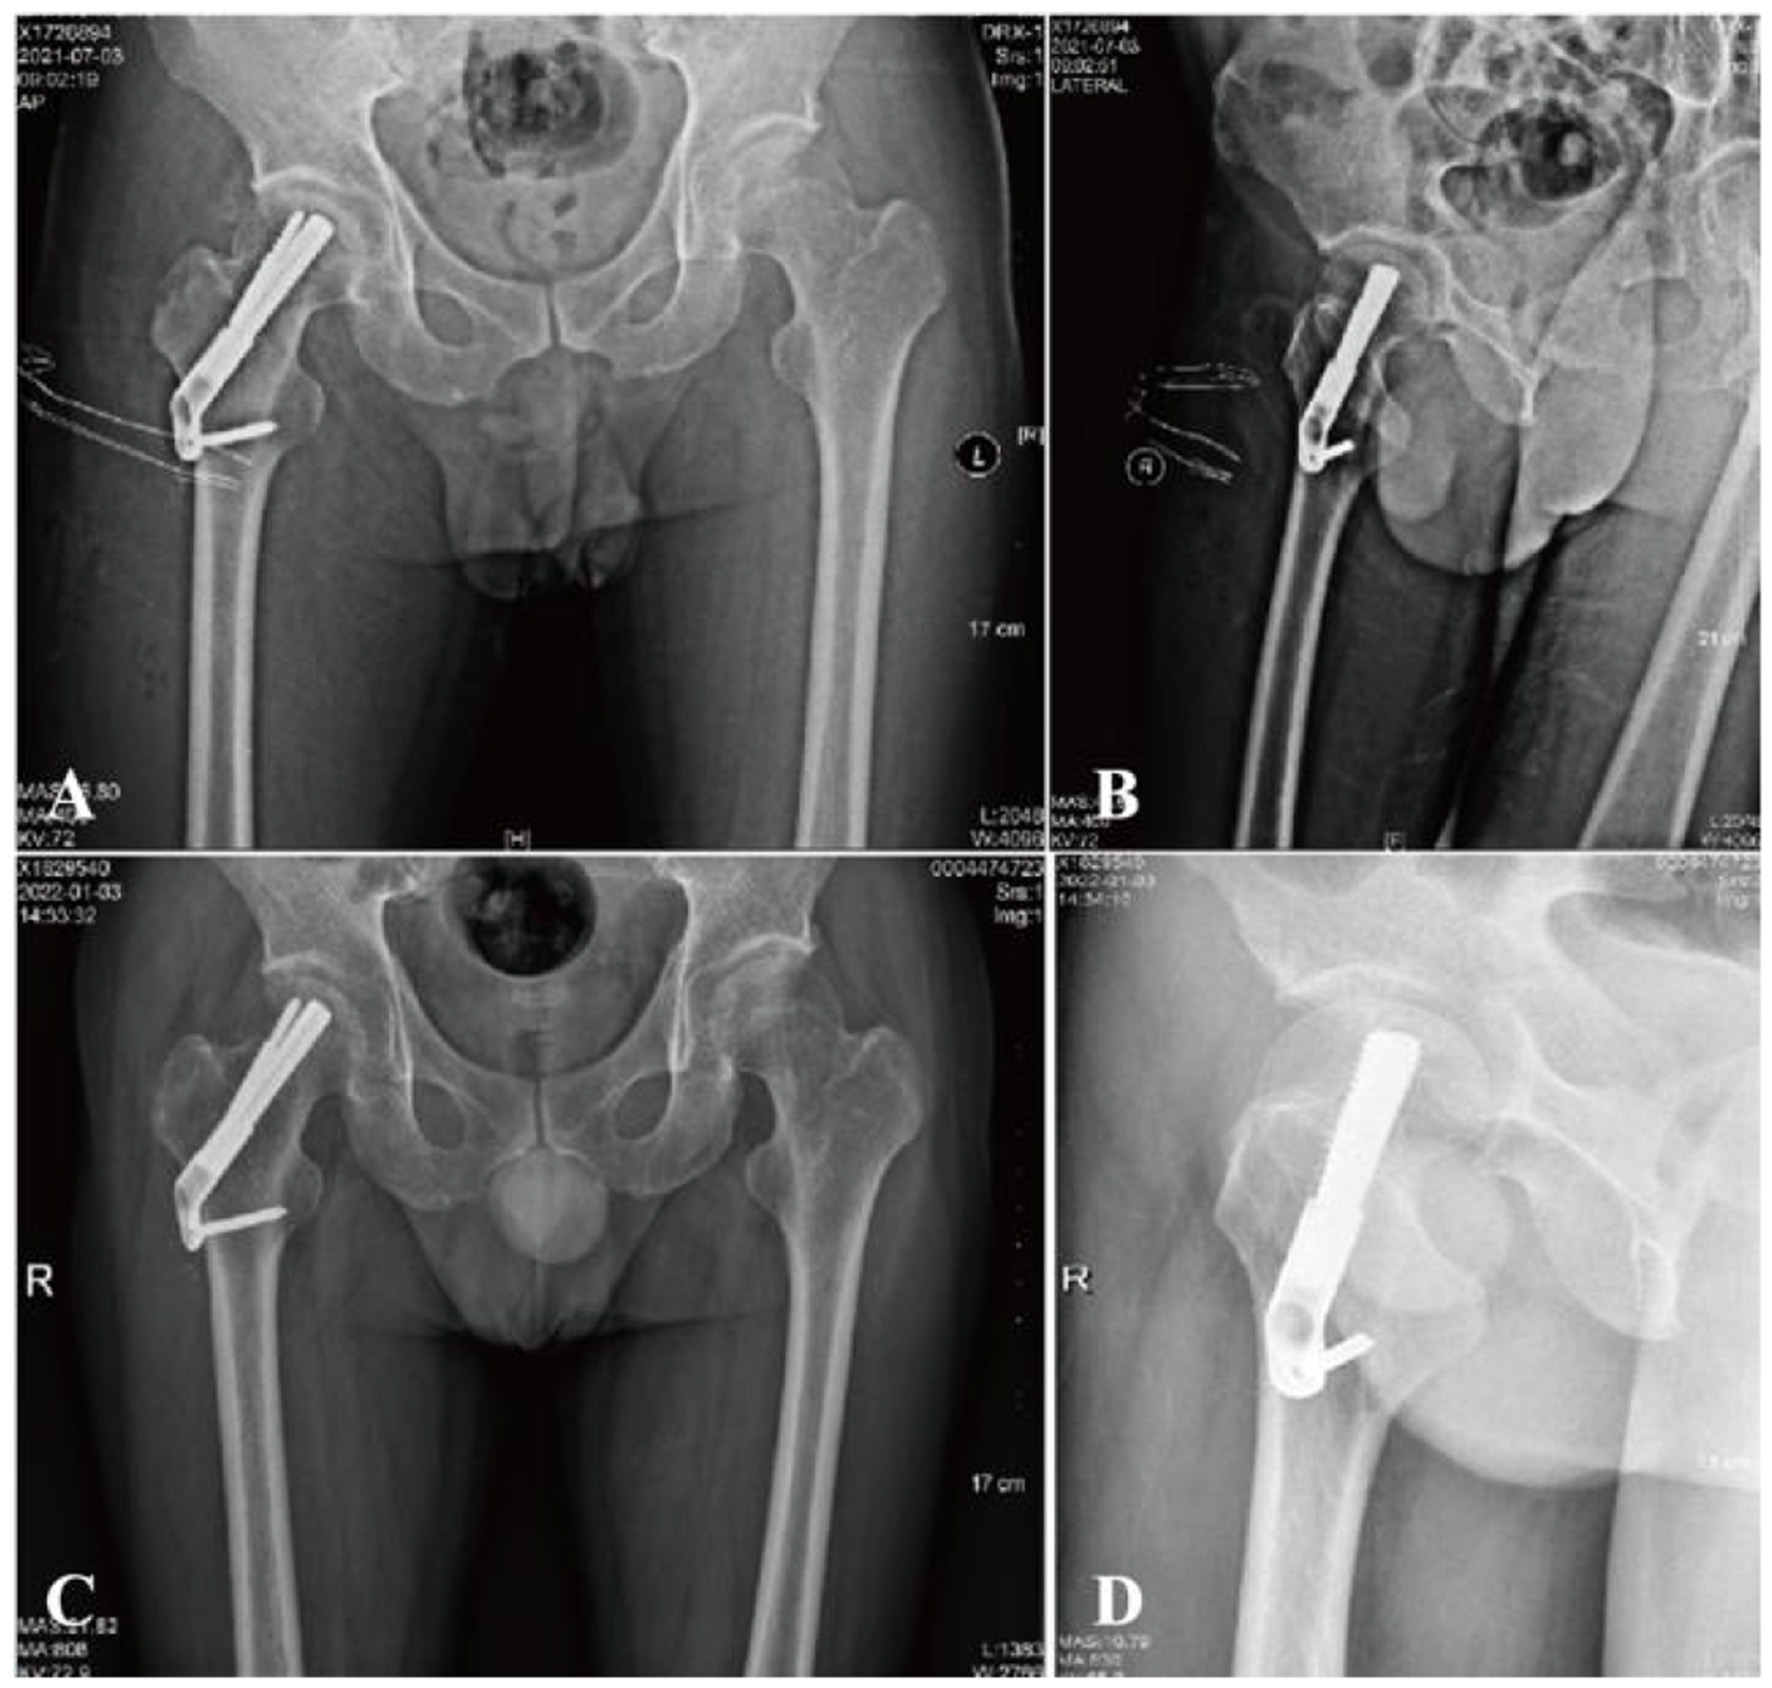

Figure 2

A 36-year-old male with femoral neck fracture. (A, B) Postoperative radiographs show good reduction (Garden Index I). (C, D) At 6 months, films confirm fracture healing with no shortening or avascular necrosis.